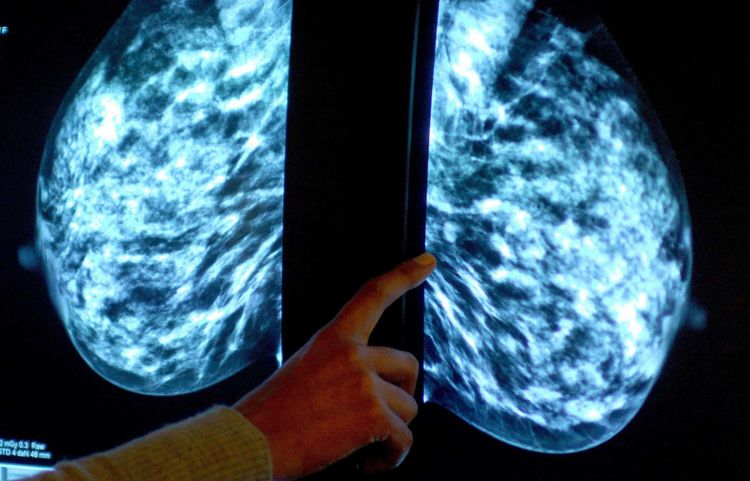

A new type of drug that blocks one of cancer’s escape routes from chemotherapy could be used to treat aggressive breast cancers, a study suggests.

A trial of the new treatment is now under way in solid tumour cancers, including aggressive triple-negative breast cancers.